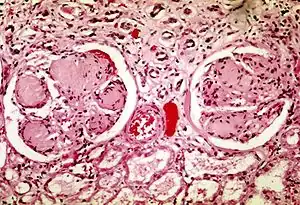

| Two glomeruli in diabetic kidney disease: the acellular light purple areas within the capillary tufts are the destructive mesangial matrix deposits. | |